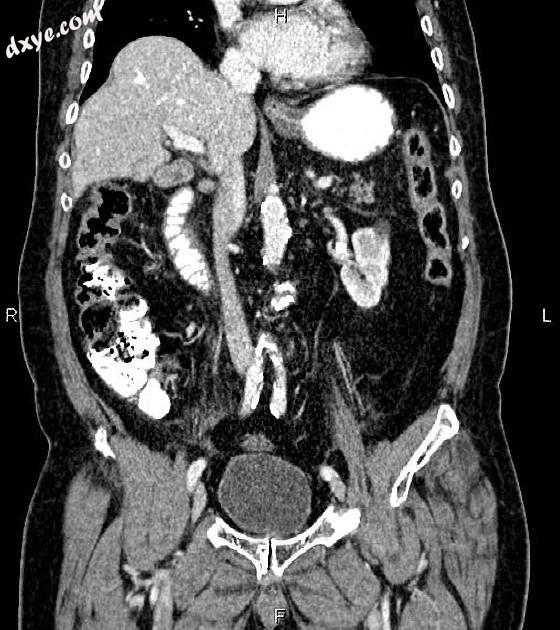

Coronal C+ portal venous phase

存在肝脏和右侧膈肌之间的结肠,推断 Chilaiditi 征。

胆囊内可见多颗小结石。

胰腺相对于患者年龄而言是突出的,建议进行胰周脂肪搁浅。

在远端胃小弯和胰腺转向架之间注意到一个 20 × 15 mm 明确定义的软组织密度肿块。小胃 GIST 可能在鉴别表中提示。

双肾可见少数非强化的单纯皮质囊肿,最大直径为28mm。

特征与急性胰腺炎相容。为患者检查淀粉酶和脂肪酶并显示显着升高。